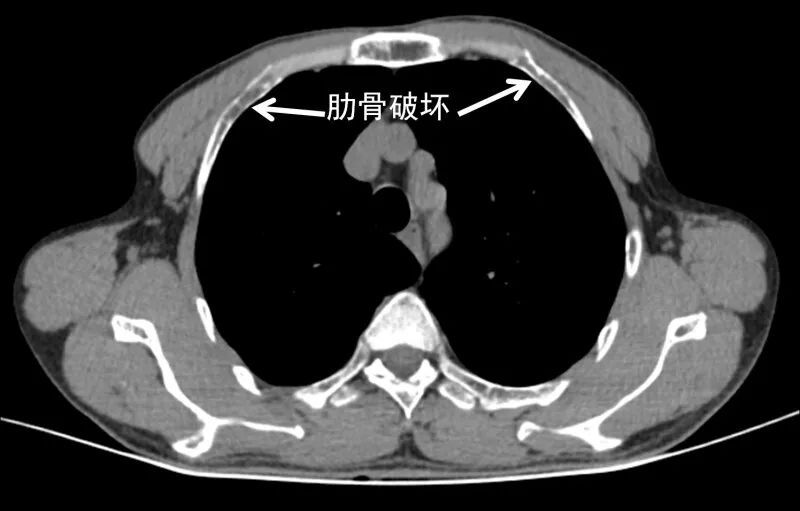

在经济发达和医疗资源丰富的地区,由于诊断意识和水平的提高,多数甲旁亢得到了早期诊断和早期治疗,这种典型的表现目前很难见到。另外还见到多处肋骨破坏(图5),这也属于甲旁亢引起的代谢性骨病,这种骨破坏很容易被误诊为恶性肿瘤骨转移。

图5.胸部CT见多处肋骨破坏